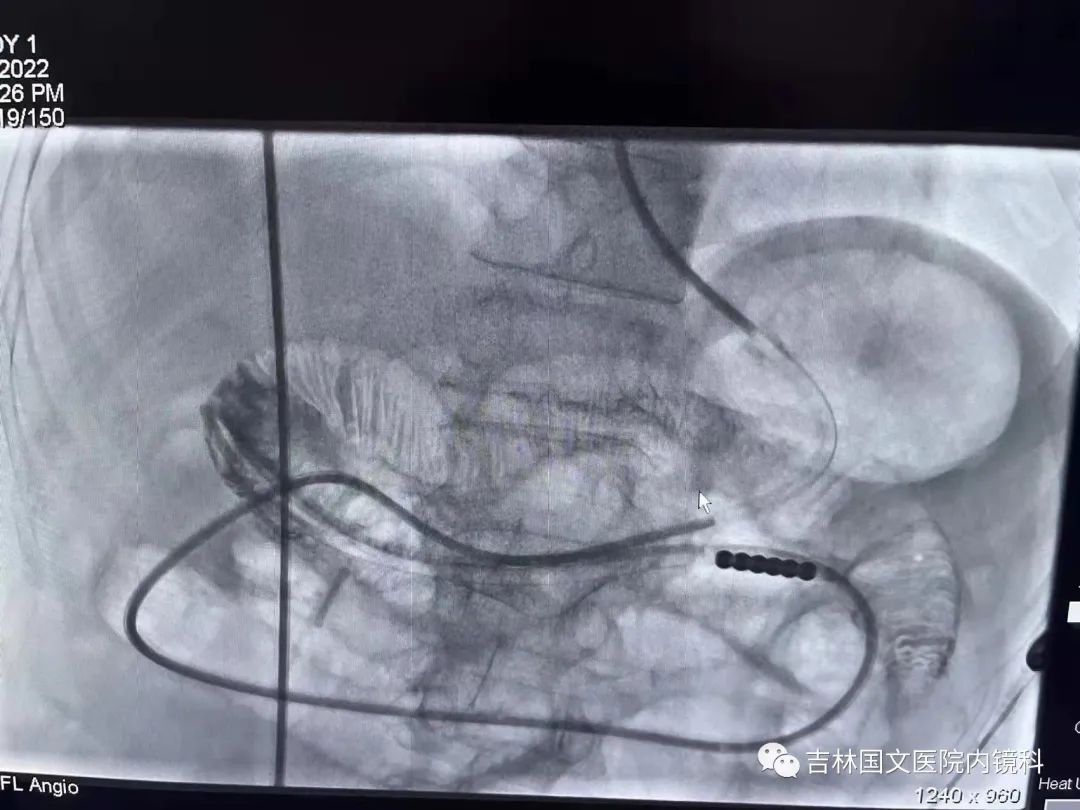

腸梗阻導(dǎo)管置入

這是一位胃術(shù)后的患者,也就是說胃內(nèi)許多正常的解剖結(jié)構(gòu)都已經(jīng)切除,這就會(huì)造成腸梗阻導(dǎo)管易迷失方向,猜測(cè)哪邊才是真正的出口是這次操作成功的關(guān)鍵,這就需要我們的“第三只眼”--胃鏡,胃鏡再加上邢主任豐富的經(jīng)驗(yàn),在一個(gè)又一個(gè)岔路口為腸梗阻導(dǎo)管引路,判斷方向,遇山開荒,遇水搭橋,即使崎嶇,只要不放棄,終將成功。